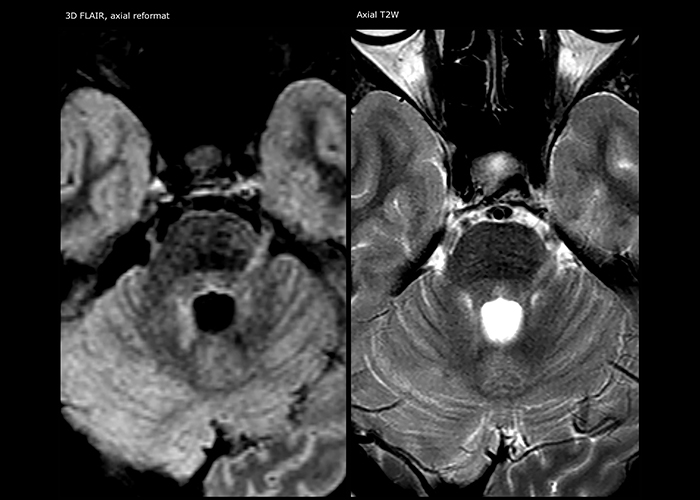

MS imaging in spine is more complicated

“For MS imaging in the spine, the basic examination includes a sagittal T2 and a post-contrast sagittal T1-weighted sequence in the whole spine. These are done in two stacks and using thin slices, for example 2 mm, without gap. As in the brain, the T2-weighted sequence visualizes the overall lesion load and helps determine if lesions are old or new. The post-contrast T1- weighted sequence helps in assessing if a lesion is new. We will sometimes add a T1 inversion recovery sequence, which has very good sensitivity, if we don’t find any lesions on T2,” Dr. Savatovsky says. “Additionally, if there is contrast enhancement outside the spine, it’s usually not MS but another kind of inflammation.”